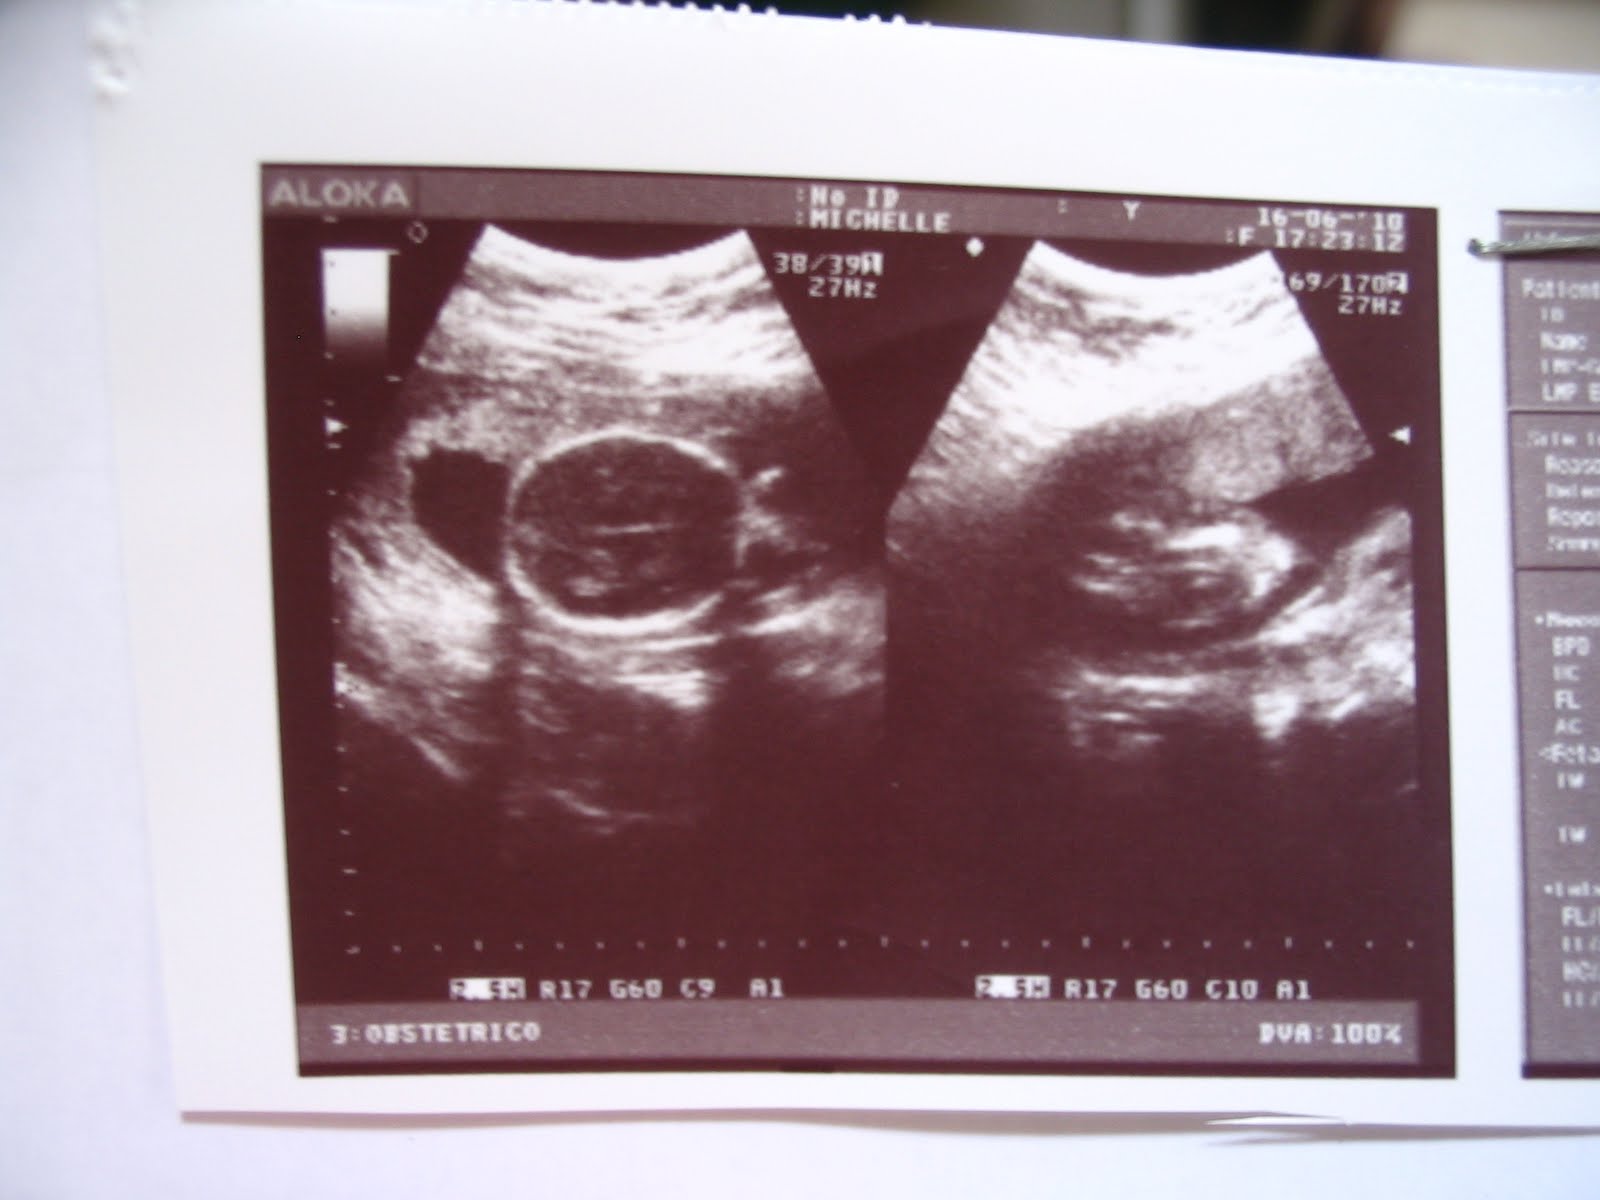

Aí, como completamos 20 semanas, fui a dra. Leilze, que vai fazer seu parto (e sua pediatra vai ser a Dra. Regina) e constatamos que você está ótima e grandona.

Olha você:

Já fica difícil de visualizar por ser grandona já!!!!

E os detalhes: